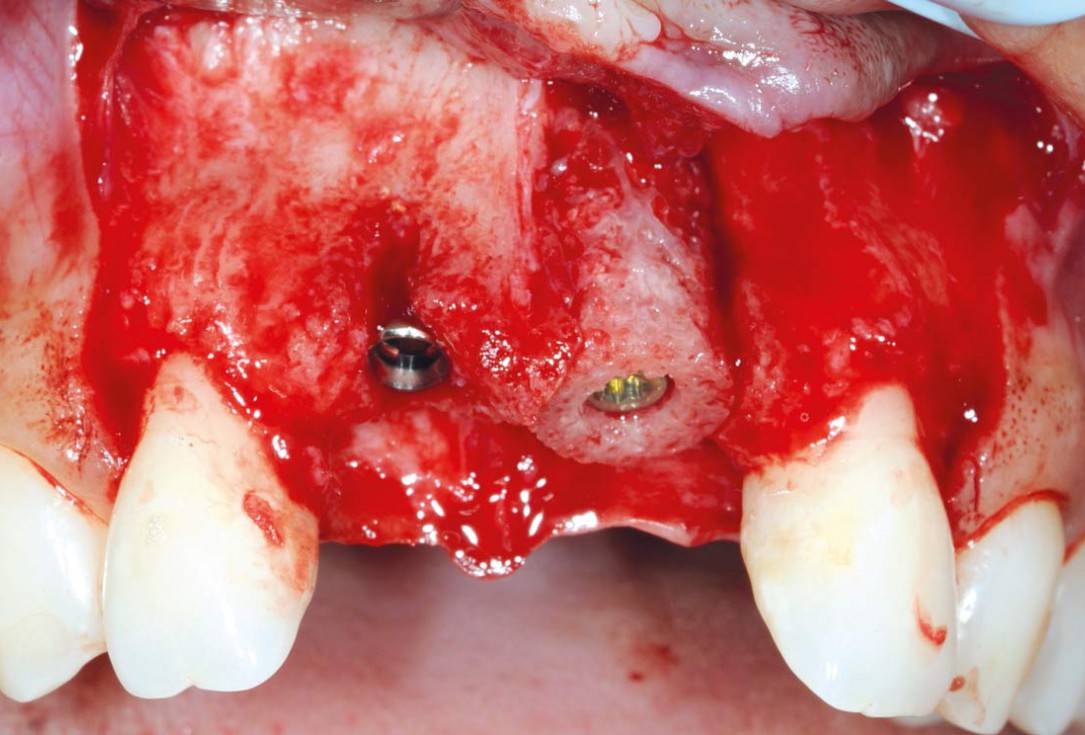

10/26 - Fixation of maxgraft® bonering with a Straumann® SLActive Bone Level Tapered ImplantBone augmentation in aesthetic zone with maxgraft® bonering - Dr. A. Patel

11/26 - Implantation in region 11Bone augmentation in aesthetic zone with maxgraft® bonering - Dr. A. Patel